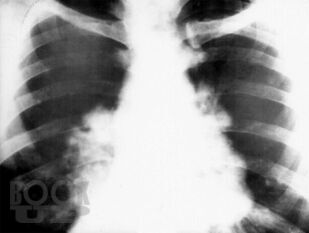

В монографии на современном научном уровне изложены вопросы истории изучения саркоидоза, представлены вопросы его этиологии, патогенеза, а также эпидемиологические, морфологические, клинические и функциональные аспекты его проявления. Авторами разработаны и внедрены в практику простые, повсеместно доступные, высокоинформативные и интегральные новые диагностические критерии оценки состояния гомеостаза у больных саркоидозом на основе оценки состояния и динамики гематологических показателей. Корректировка показателей гомеостаза (типов адаптационных реакций организма, типов реактивности организма, лейкоцито-лимфоцитарного индекса, показателей энтропии и избыточности форменных элементов белой крови и показателей белковых фракций крови) позволила внедрить в практическую работу математические модели и графики факторных пространств для проведения персонифицированного назначения активаторов защитных систем организма, контроля активационной патогенетической терапии и повысить эффективность лечения саркоидоза.

Монография может быть полезна для врачей-терапевтов, пульмонологов, рентгенологов, дерматологов, а также для врачей-интернов различных специальностей, клинических ординаторов и студентов старших курсов медицинских вузов.